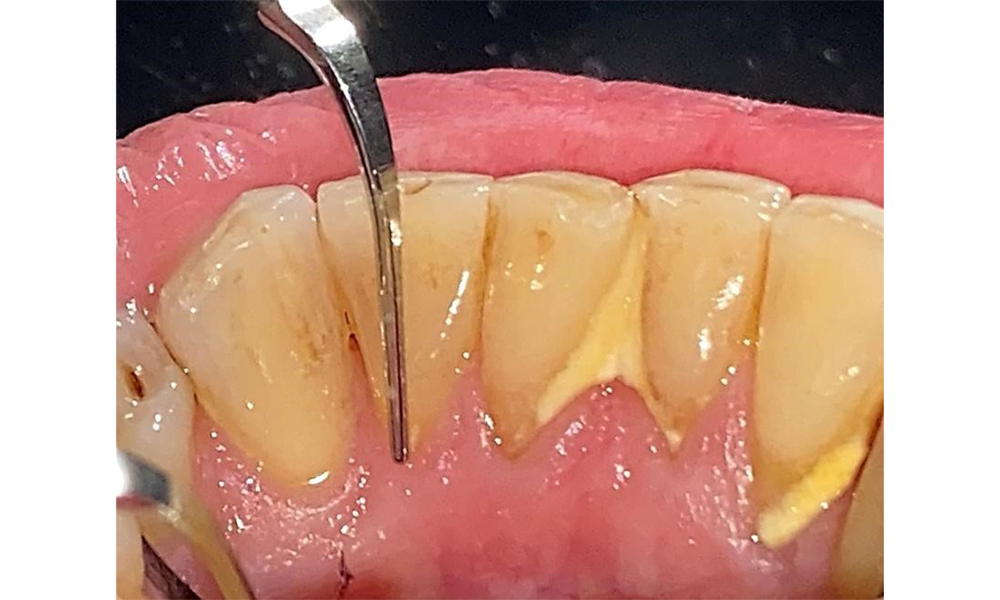

Supragingival and subgingival biofilm removal is indispensable for maintaining the stability of the periodontal condition. Air polishing using low-abrasive powder is suitable for this purpose. Periodontal pockets and exposed root surfaces must be cleaned with low-abrasion powders. The use of a flexible parotip is recommended for patients with increased probing depths (deeper than 5 mm) (Fig. 10). (9)

Subgingival application of the flexible air polisher tip (Proxeo Aura, W&H, shown here) to the mesiopalatal aspect of tooth 27 with a periodontal pocket depth of 5 mm.

Fig. 10: Subgingival application of the flexible air polisher tip (Proxeo Aura, W&H, shown here) to the mesiopalatal aspect of tooth 27 with a periodontal pocket depth of 5 mm. © Dr R. Krapf